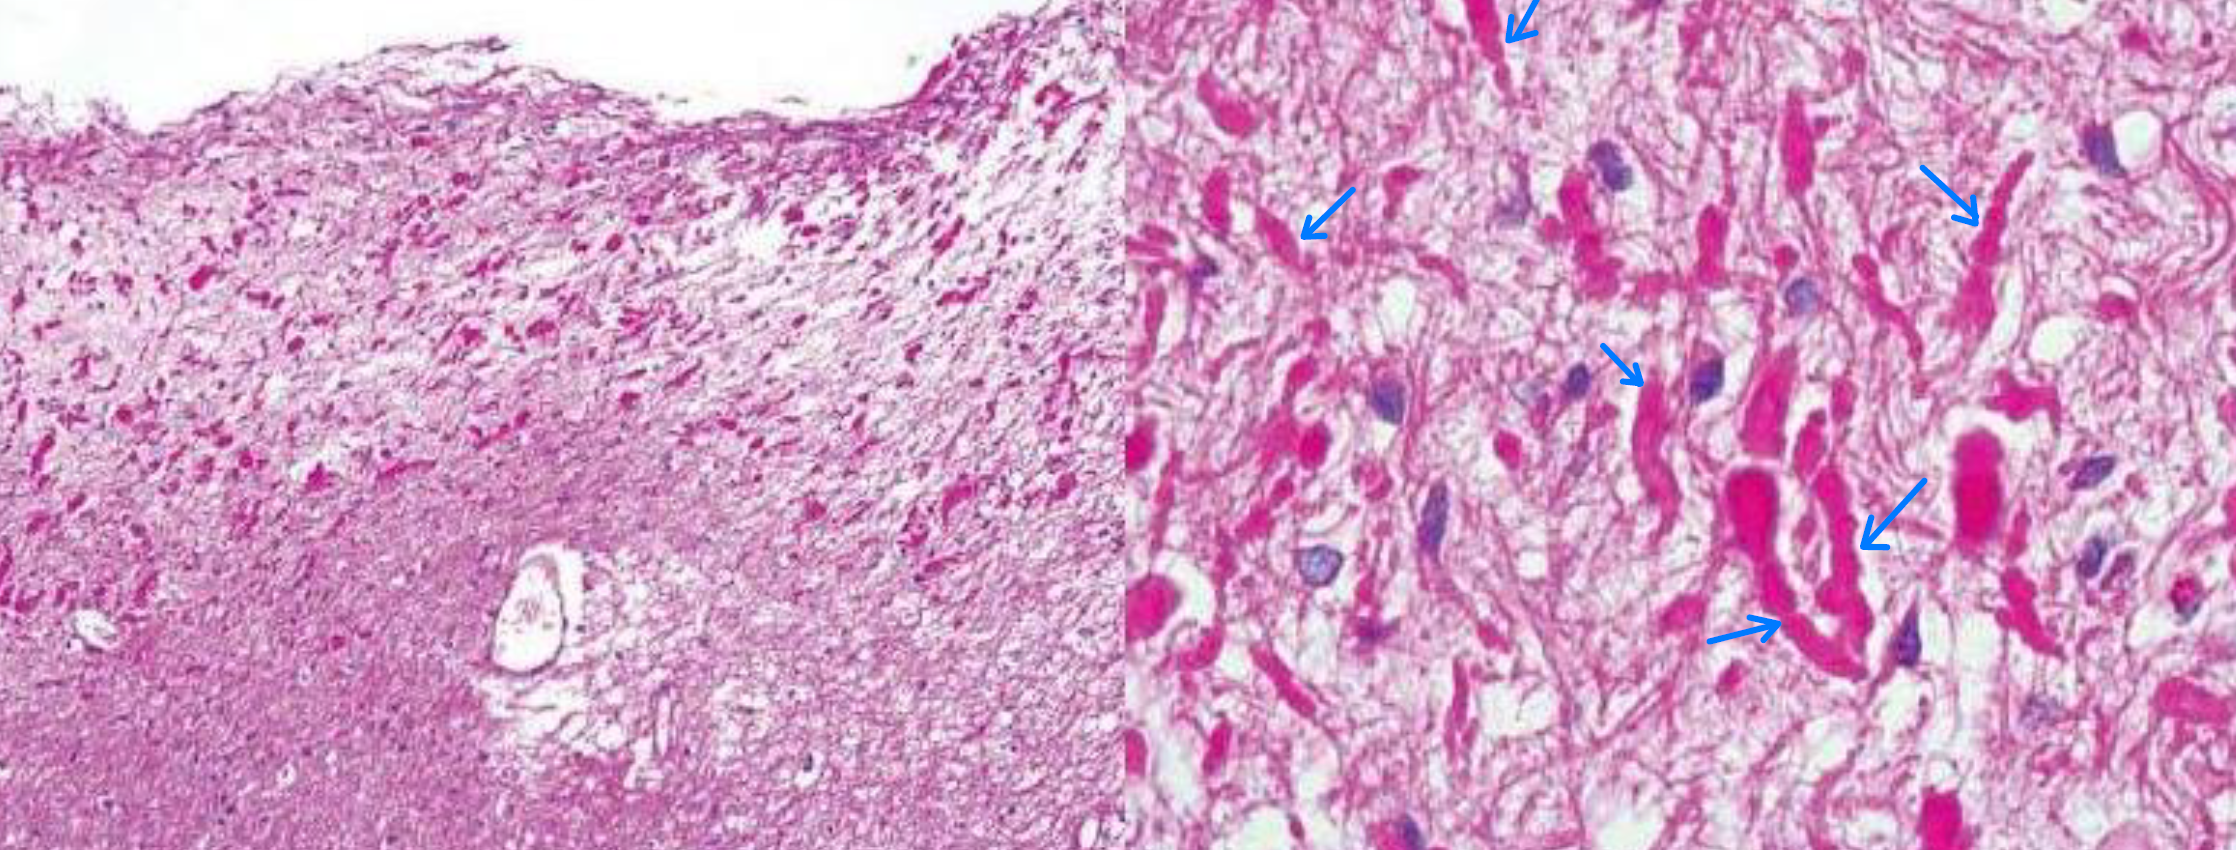

glioblastoma (교모세포종)

- IDH-wild type, TERT mutation이 관찰된다.

- IDH는 야생형인데도 grade 4로 예후가 가장 나쁘다.

pilocytic astrocytoma

- 빈 공간(microcyst)과 빨간색 rosenthal fiber가 특징적이다.

- BRAF-mutant이고 grade 1로 예후가 좋다.